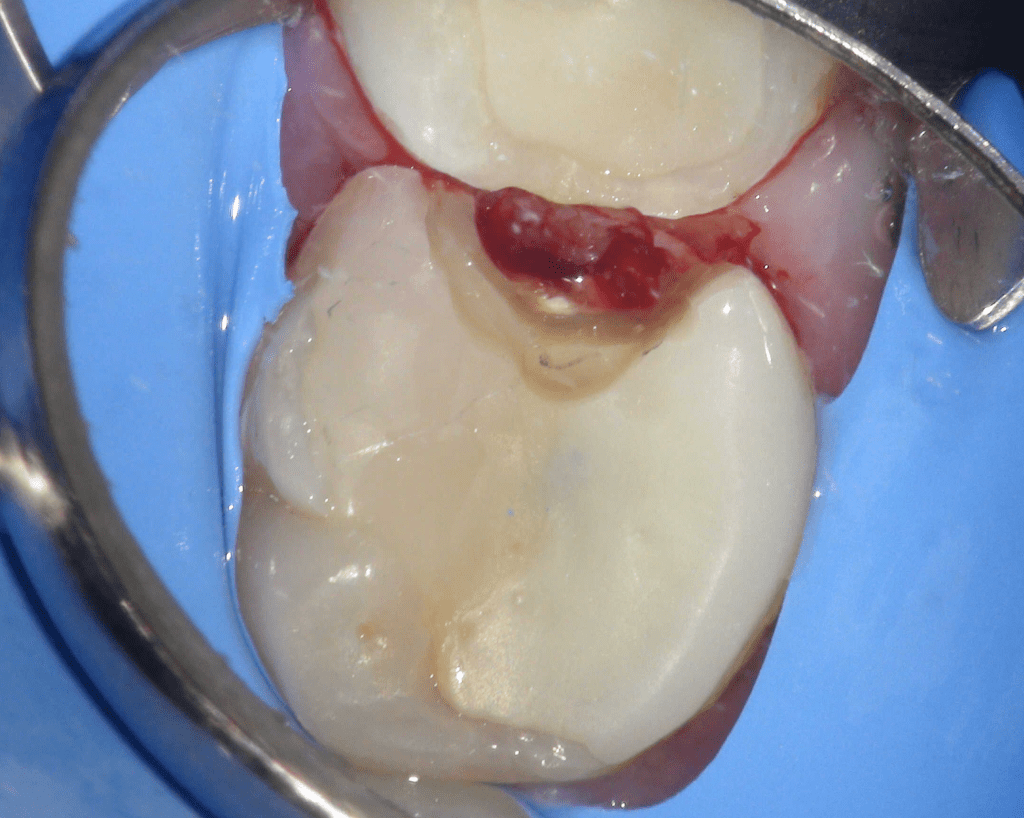

Pulpotomía biodentine + reco preendio